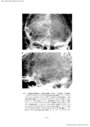

第3脳室近傍腫瘍の神経放射線診断-脳血管撮影を中心に- III 主に第3脳室の側方に発育する腫瘍(2)